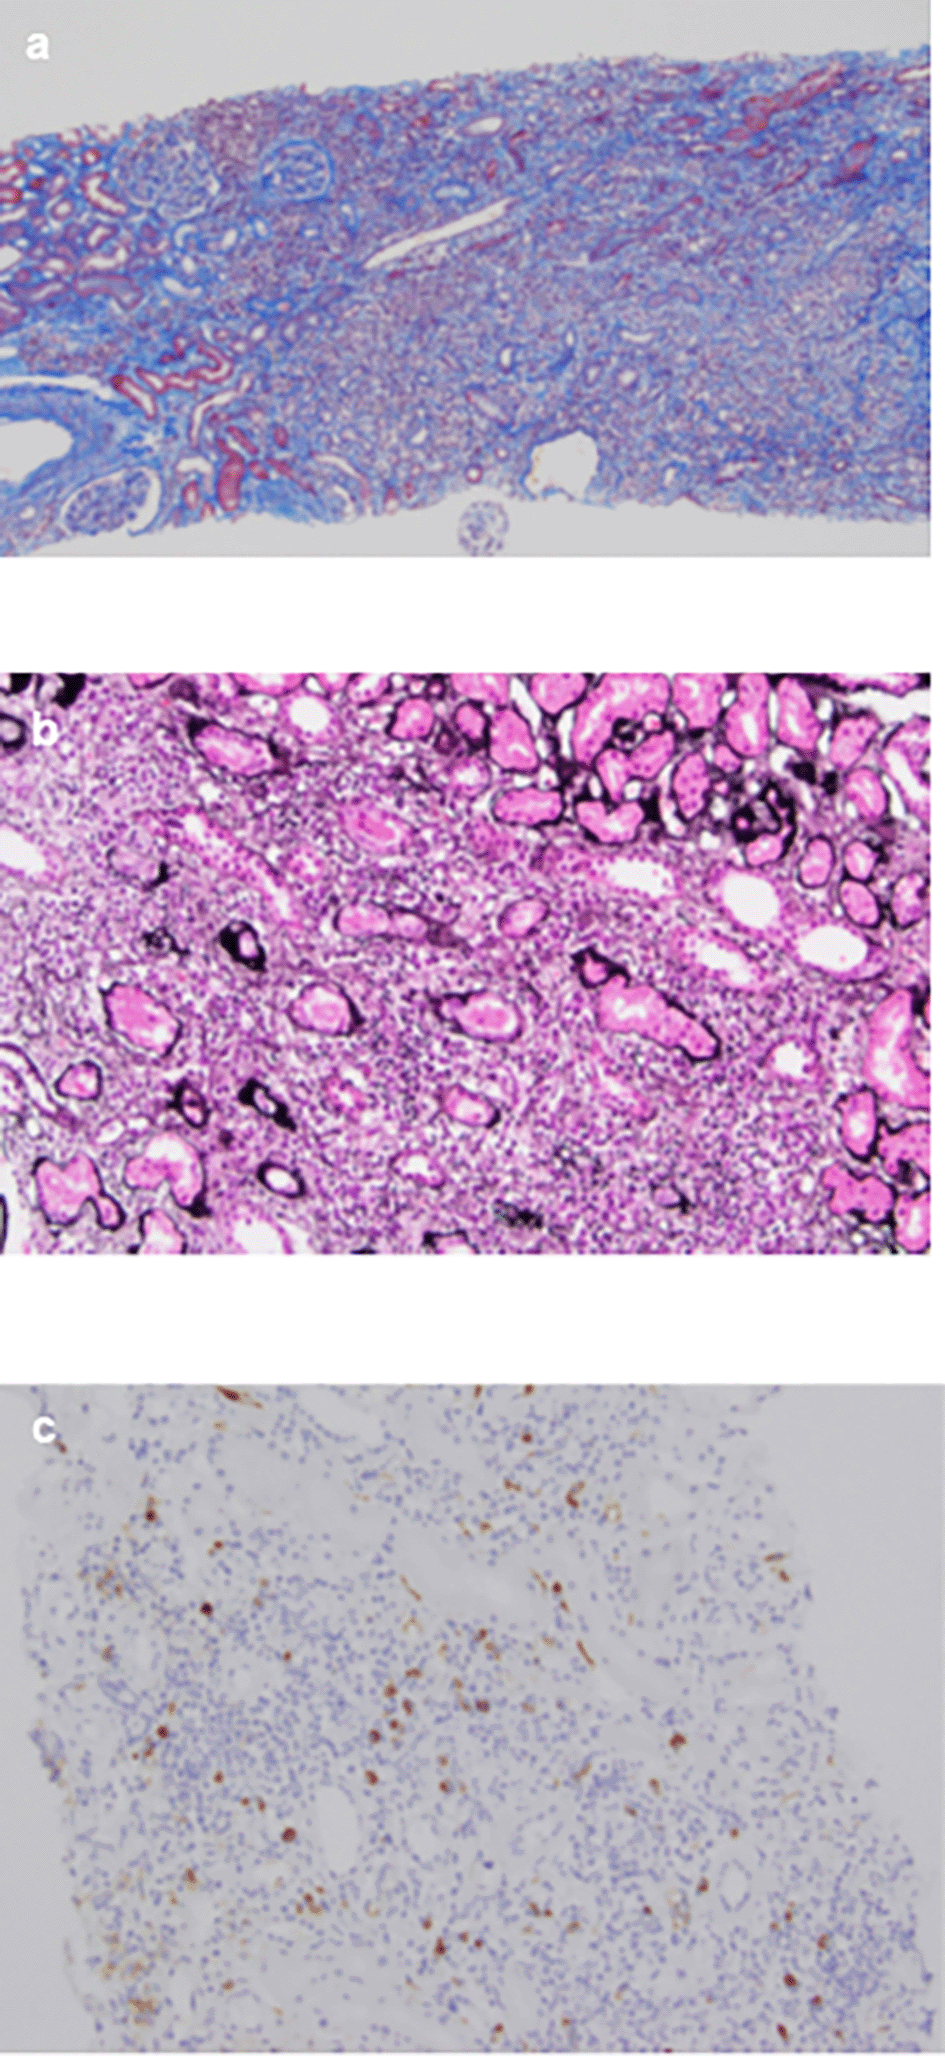

An 84-year-old unemployed Japanese man presenting with dyspnea on exertion and cough was referred to our hospital. The patient had a history of hypertension and hypothyroidism, but an unremarkable family history of any related pathology. Examination results of the patient were found to be negative for arthralgia, skin rash, macrohematuria, and hemoptysis. Upon admission, body temperature was recorded to be 36.5 °C; blood pressure, 128/72 mmHg; heart rate, 72 bpm; oxygen saturation, 98%; weight, 60.5 kg; height, 164.9 cm; and BMI, 21.1 kg/m2. Initial laboratory and diagnostic workup revealed blood urea nitrogen 18 mg/dL (normal range: 8-20 mg/dL), creatinine 0.98 mg/dL (normal range: 0.65-1.07 mg/dL), estimated glomerular filtration rate 56 mL/min/1.73 m2 (normal range: ≥ 60 mL/min/1.73 m2), calcium 9.4 mg/dL (normal range: 8.8-10.4 mg/dL), total protein 9.1 g/dL (normal range: 6.5-8.0 g/dL), albumin 3.6 g/dL (normal range: 3.9-4.9 g/dL), alkaline phosphatase 60 IU/L (normal range: 50-350 IU/L), aspartate transaminase 27 IU/L (normal range: 7-38 IU/L), alanine transaminase 11 IU/L (normal range: 4-44 IU/L), total cholesterol 182 mg/dL (normal range: 120-220 mg/dL), triglyceride 175 mg/dL (normal range: 50-149 mg/dL), WBC 11.5×103/μL (normal range: 3.1-8.4×103/μL), RBC 3.97×106/μL (normal range: 4.2-5.7×106/μL), hemoglobin 12.5 g/dL (normal range: 14-18 g/dL), platelets 200×103/μL (normal range: 150-330×103/μL), eosinophils 3% (normal range: 0-5%), and urinalysis negative for protein, RBC, and cell casts. Urinary N-acetyl-beta-D-glucosaminidase (NAG)/creatinine 17.1 IU/gCr (normal range: 1.6-5.8 IU/gCr) and urinary β2 microglobulin 371 mg/L (normal range: ≤289 mg/L). Antineutrophil cytoplasmic antibodies screening was found to be negative, with low C3=68 mg/dL, low C4=7.4 mg/dL, and negative for anti-SSA, anti-SSB, anti-RNP, Scl-70, anti-Sm, and ds-DNA antibodies. Antinuclear antibodies (ANA) antibodies were found to be ×1280. Hyperglobulinemia was determined with an IgG level of 3719 mg/dL (normal range: 870-1700 mg/dL) and an IgG4 level of 1290 mg/dL (normal range: 4-108 mg/dL). Rheumatoid factor (≤15 IU/mL) was elevated at 24 IU/mL, and KL-6 (<500 IU/mL) was significantly increased at 623 IU/mL. Computerized tomography (CT) revealed bilateral ground-glass and reticular opacities predominantly in the lower and peripheral portions of the lungs (Figure 1a). Furthermore, bronchial wall thickening, and enlarged cervical, mediastinal, and axillary lymph nodes were identified. However, renal, pancreatic, or salivary gland inflammation was not observed. Ga-67 scintigraphy revealed accumulation in the kidneys (Figure 2). Consequently, the patient was diagnosed with IgG4-related kidney disease based on the renal pathology with massive tubulointerstitial nephritis, characteristic fibrosis (bird’s eye pattern) (Figure 3a and b), and IgG4-positive cell infiltration, wherein the number of IgG4 positive plasma cells was >10/hpf, and IgG4/IgG ratio was 61.9% (Figure 3c). Deposition of globulin or complement, and evidence of glomerular sclerosis were not observed in the glomeruli. Treatment was initiated by administering oral prednisolone at 30 mg/day for one month, followed by prompt alleviation of cough and dyspnea on exertion. With a subsequent decrease (after one month prednisolone treatment) in urinary NAG and β2 microglobulin and IgG4 levels, prednisolone was decreased from 2.5 to 5 mg every 2 to 4 weeks for 4 weeks. One year after the initiation of treatment, the patient achieved normalization of serum IgG4 levels, and chest CT revealed the interstitial pattern was found to have nearly disappeared (Figure 1b). Figure 4 shows the clinical course of this patient.

(a) The interstitium shows mononuclear cell infiltration and interstitial fibrosis with tubular atrophy with Masson’s trichrome stain (×40); (b) PAM stain in the interstitium shows bird’s eye pattern of fibrosis (×200); (c) Immunohistochemical analysis for IgG4 shows dominant IgG4+ plasma cell filtration, with an IgG4+/IgG+ ratio of >40% (×100).